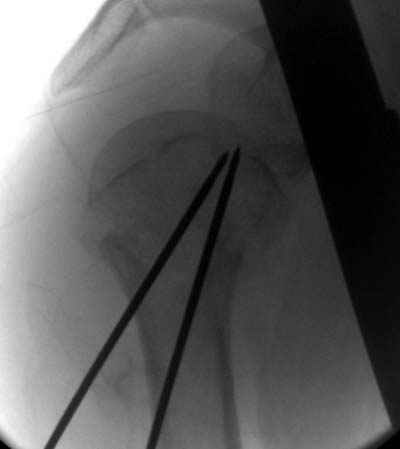

Djoldas Kuldjanov 30 Ноябрь 2004, 23:36

Случай интересный и заслуживает внимания со своей актуальностью, потому что открывать такие переломы вряд ли кому доставит удовольствие, даже тем, кто владеют АО или locking concept technique.

Учитывая отсутствие знаний о методике, хотя я очень заинтересовался, после прошлегодного доклада из ЦИТО в Ст. Петерсбурге, простота методики и отсутствие миграции спиц распологает к себе.

Интересно знать, какого диаметра спицы пригодны для фиксации?

Пока я пользуюсь методикой принятой у нас (методика Сиэтла), также перкутанный спицевой метод, только сцицы 2.8 мм с резбой на конце.

Здесь случай перелома-вывиха плеча, больному 56 лет, после "дважды" закрытой неудачной репозиции, опять же ургентно взяли в операционную, после полного общего обезболивания попытались сделать репозицию, и фиксацию провели спицами.

Больной находился в повязке, примерно напоминяющей косыночную, рекомендованы движения в локтевом суставе и маятниковые движения в плече, спицы удалены в три недели (были случаи миграции)

Больной амбулаторный, предупрежден на случай осложнения АВН головки.